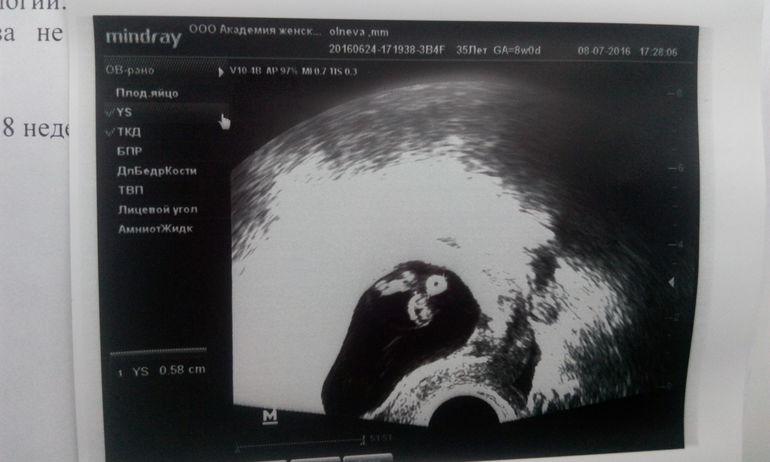

Вчера была на узи, нам 8 недель))) КТР 16 мм, ПЯ 41.6 мм, ЖМ 5.8мм .СБ 143 удара в минуту. Надеюсь и дальше все будет хорошо.